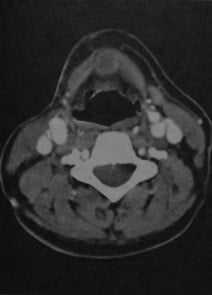

Щитовидно-язычная киста. КТ с контрастированием. Киста расположена по средней линии сразу под подъязычной костью между щитоподъязычными мышцами. Содержимое кисты имеет несколько меньшую плотность, чем мышцы, и окружено тонкой усиленной капсулой. Киста не достигает кожи и является случайной находкой.